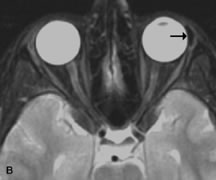

Inflammatory and Lymphoproliferative Lesions

Inflammatory conditions of the orbit, both idiopathic (inflammatory pseudotumor) and those of known causes, have been found to be hypointense to fat and isointense to muscle on Tl-weighted studies and isointense or slightly hyperintense to fat on T2-weighted images (Fig. 21).50,64,69 The more fibrous or sclerosing varieties have less signal intensity on T2-weighted images. Marked enhancement is seen in pseudotumor infiltrates after gadolinium administration.70 The same signal characteristics are demonstrated in patients with Tolosa-Hunt syndrome, with mass lesions seen in the cavernous sinuses and orbital apices.71

Fig. 21. A. T1-weighted MR scan demonstrates diffuse enlargement of both the superior rectus and levator palpebrae superioris muscles (single arrows). The involvement of the tendinous insertions and preseptal soft tissues (open arrows) as well as lack of involvement of other muscles helps differentiate this entity from thyroid-associated orbitopathy. B and C. Postcontrast fat-suppressed T1-weighted MR scans demonstrate extensive enhancement of the involved muscles as well as the preseptal (open arrows) and perinuscular tissues (double arrows).

Lymphomas have MRI characteristics similar to those of inflammatory lesions in that they are hypointense to fat and isointense to muscle on T1-weighted images (Fig. 22). They may appear hyperintense to fat on T2-weighted images, perhaps owing to less fibrosis than that seen in orbital inflammatory pseudotumor, although this is not a consistent finding.31,50,66 Lymphoid tumors typically enhance moderately after contrast injection. Unfortunately, studies have shown that tumor density and homogeneity are similar between inflammatory and malignant orbital infiltrates, and MRI cannot differentiate these lesions.72,73

Fig. 22. A and B. T1- and (C) T2-weighted MR scans demonstrate a poorly defined multicompartmental mass enveloping the lateral rectus, superior rectus, and levator palpebrac superioris muscles. The lesion is isointense to brain on T1- and T2-weighted scans, as is typical for highly cellular neoplasms. D. Postcontrast fat-suppressed T1-weighted scan demonstrates intense enhancement of the infiltrating intraconal and extraconal tumor.